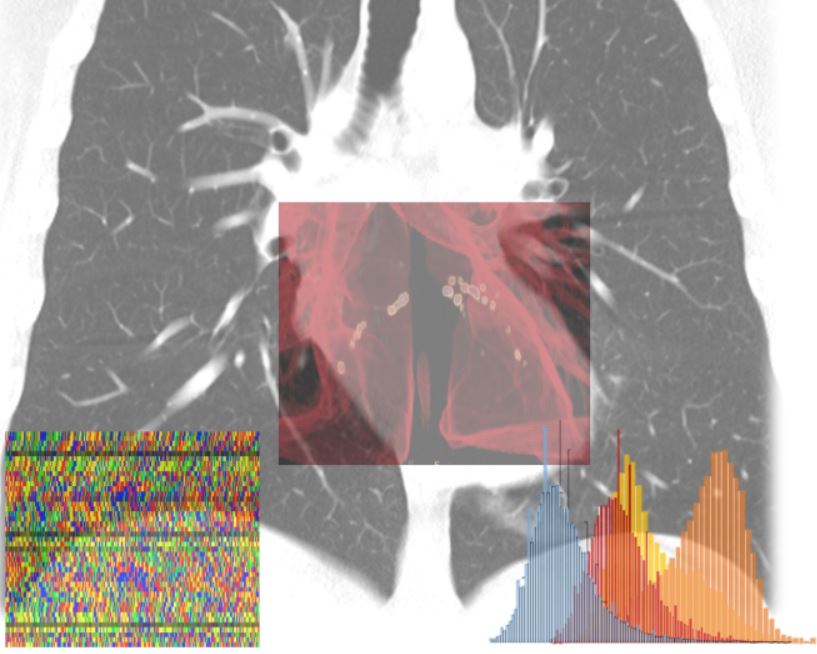

MILANO (ITALPRESS) – Una piattaforma di apprendimento autonomo in grado di calcolare per ogni individuo – sulla base di una serie di indicatori clinici e diagnostici – la probabilita’ di sviluppare le forme piu’ gravi di Covid-19, permettendo cosi’ interventi sanitari mirati e tempestivi e riducendo l’impatto sul sistema sanitario. E’ questo l’obiettivo del progetto AI-SCoRE (acronimo di Artificial Intelligence – Sars Covid Risk Evaluation) ideato dai professori Carlo Tacchetti e Antonio Esposito, entrambi docenti dell’Universita’ Vita-Salute San Raffaele, rispettivamente direttore e vice-direttore del Centro di Imaging Sperimentale dell’IRCCS Ospedale San Raffaele di Milano, e sviluppato in collaborazione con due colossi mondiali dell’information technology come Microsoft e NVIDIA, con il Centro di Omics Sciences dell’IRCCS Ospedale San Raffaele diretto dal dottor Giovanni Tonon, e con il supporto di due aziende: Orobix srl, societa’ attiva nell’ingegneria, produzione e governance di sistemi di AI con esperienza decennale e internazionale in ambito healthcare e Porini, centro di eccellenza e partner internazionale di Microsoft sulle piattaforme Cloud Azure e sulle soluzioni di Advanced Analytics.

La raccolta dei dati di oltre 2000 pazienti – reclutati fra Ospedale San Raffaele, Ospedale Bolognini di Seriate e Centro Cardiologico Monzino – e’ gia’ iniziata, cosi’ come la costruzione dell’infrastruttura software su cui poggera’ l’algoritmo.